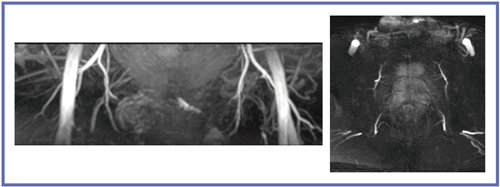

東芝の非造影技術である“Time-SLIP法”は,RFパルスによるラベリングで造影剤を使用することなく血流を描出するが,前立腺領域では骨盤から前立腺周囲への血管が明瞭に描出される(図4)。Time-SLIP法の信号は,T1緩和時間や血流などさまざまな情報を含んだものであり,今後の検討が重要と考える。